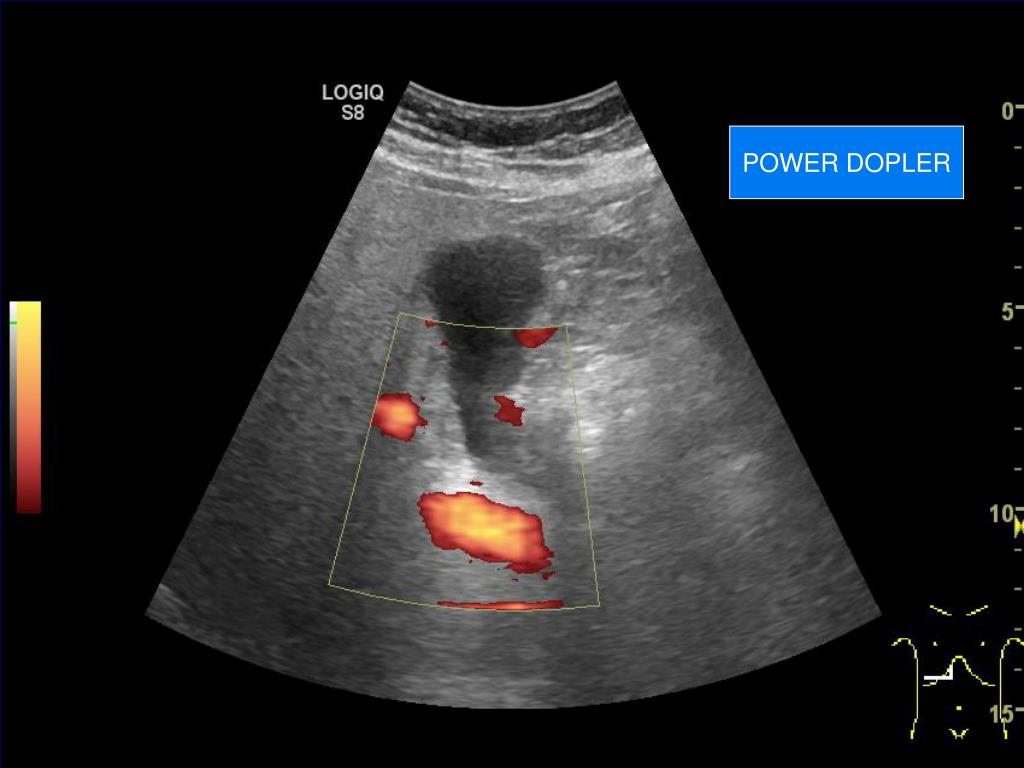

18. POWER DOPLER